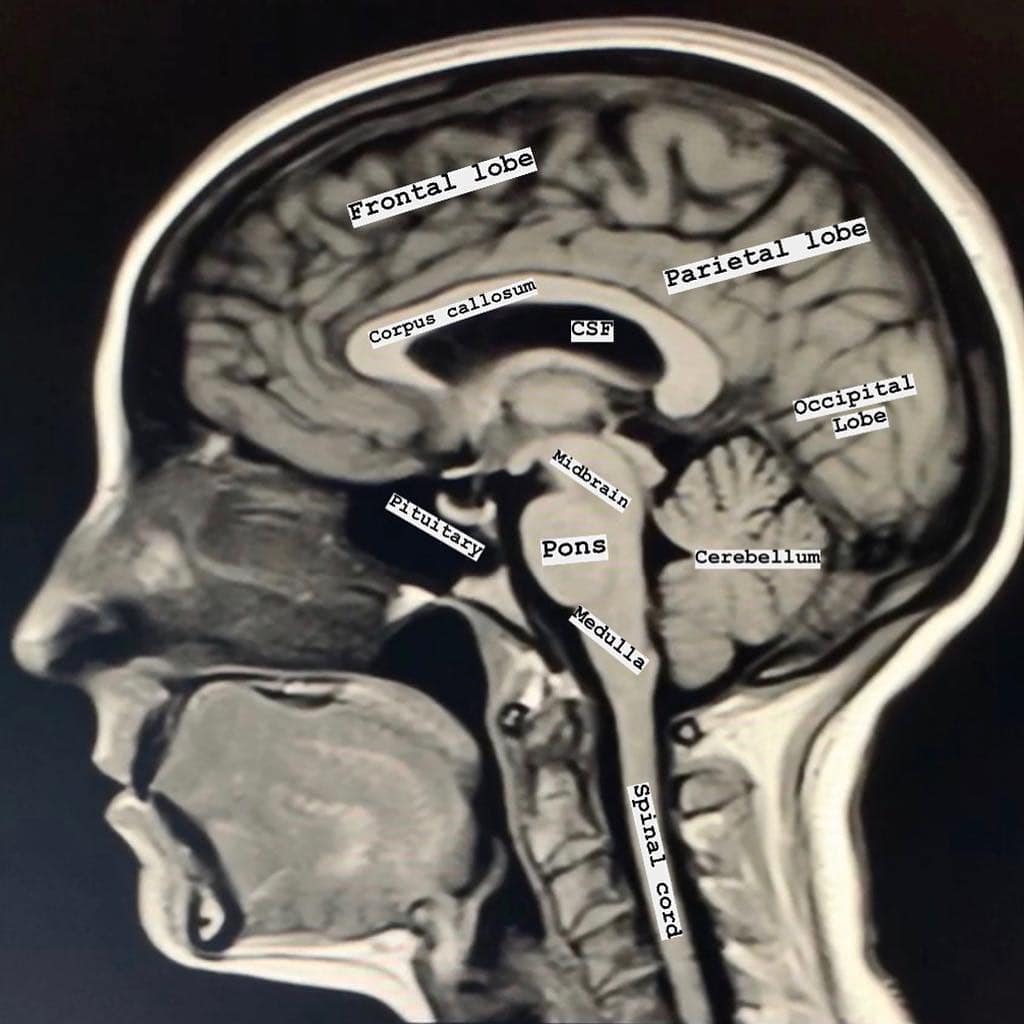

MEDICO RADIOLOGO